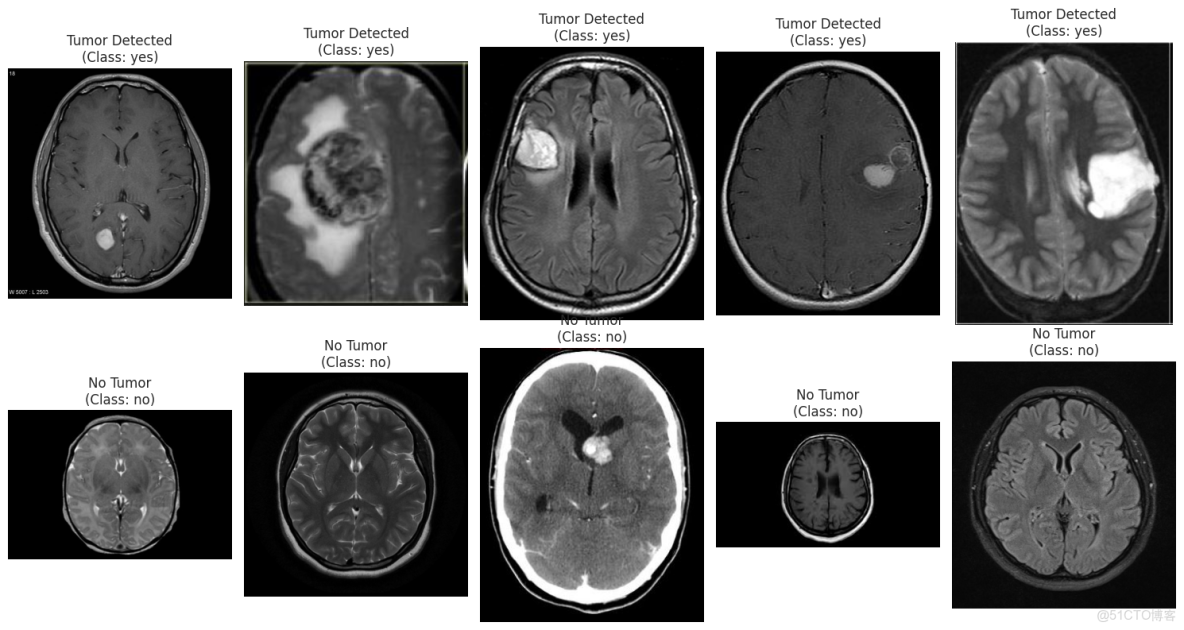

查看腫瘤和非腫瘤圖片

plt.figure(figsize=(15, 8))

n_samples = 5

yes_samples = df[df['label'] == 'yes'].sample(n_samples)

for i, row in enumerate(yes_samples.iterrows()):

filepath = row[1]['filepath']

img = cv2.imread(filepath)

img = cv2.cvtColor(img, cv2.COLOR_BGR2RGB)

plt.subplot(2, n_samples, i + 1)

plt.imshow(img)

plt.title(f"Tumor Detected\n(Class: yes)")

plt.axis('off')

no_samples = df[df['label'] == 'no'].sample(n_samples)

for i, row in enumerate(no_samples.iterrows()):

plt.subplot(2, n_samples, n_samples + i + 1)

plt.title(f"No Tumor\n(Class: no)")

plt.tight_layout()

plt.show()

深度學習實戰-基於Vision Transformer的腦腫瘤MRI圖像識別_Image_03